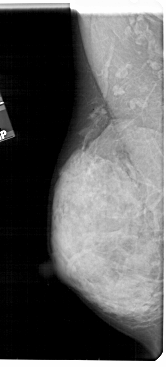

A_1807_1.LEFT_MLO

LEFT_MLO LINES 5491 PIXELS_PER_LINE 2476 BITS_PER_PIXEL 12 RESOLUTION 43.5 NON_OVERLAY